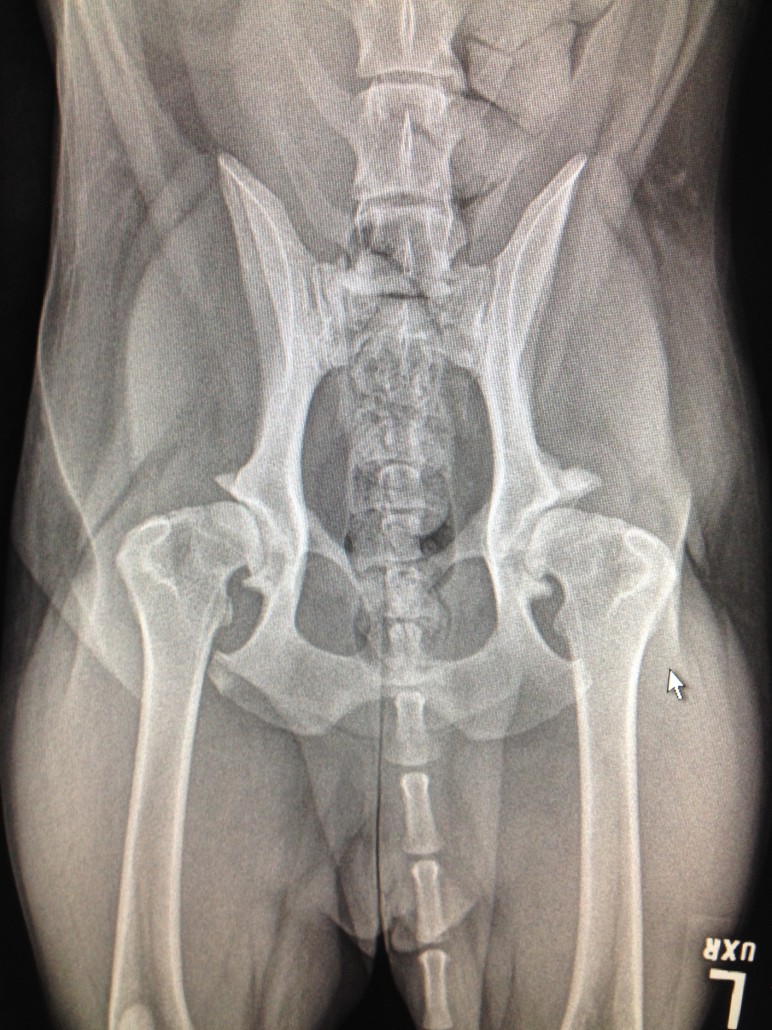

Les deux radiographies montrent des hanches avec une laxité articulaire. Ce sont les premiers signes de dysplasie. On observe souvent ce type de radiographie chez de jeunes chiens dysplasiques. Les têtes fémorales ne sont pas bien enfoncées dans l’articulation. L’espace articulaire est inégal. Les rebords osseux sont encore lisses démontrant encore peu d’ostéoarthrose, qui ne manquera toutefois pas d’arriver avec les années.